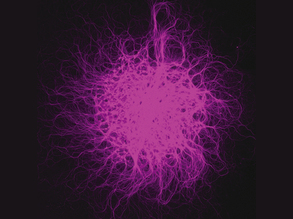

Spotlight on Microglia